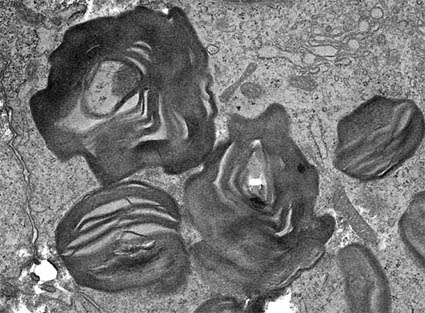

Electron microscopy

The characteristic change in men consists of diffuse irregularities of the GBM with variation in the thickness and variable appearance of the dense lamina, with lucid and electron-dense zones that give it a basket and multilaminated appearance; there may be finely laminar material in the lucid zones. There are zones of frank thickening that alternate with other thinned ones; defects are detected due to discontinuity of the GBM, which causes the endothelial and epithelial cells to appear almost together. In young men and in women there may be a diffuse thinning without the multilaminated appearance of adults, with changes similar to those of thin basement membrane condition. There may be similar changes in the basal tubular membranes and Bowman's capsule. As glomerular disease progresses there is usually progressive loss (or fusion) of podocyte processes.

Figure 5. Irregular basement membranes, with laminations, very thickened areas alternating with very thin ones. EM, original magnification, X4,000.

Figure 6. In this image, the laminations of the basement membrane are more evident in a case of X-linked Alport. Original magnification, X4,000.